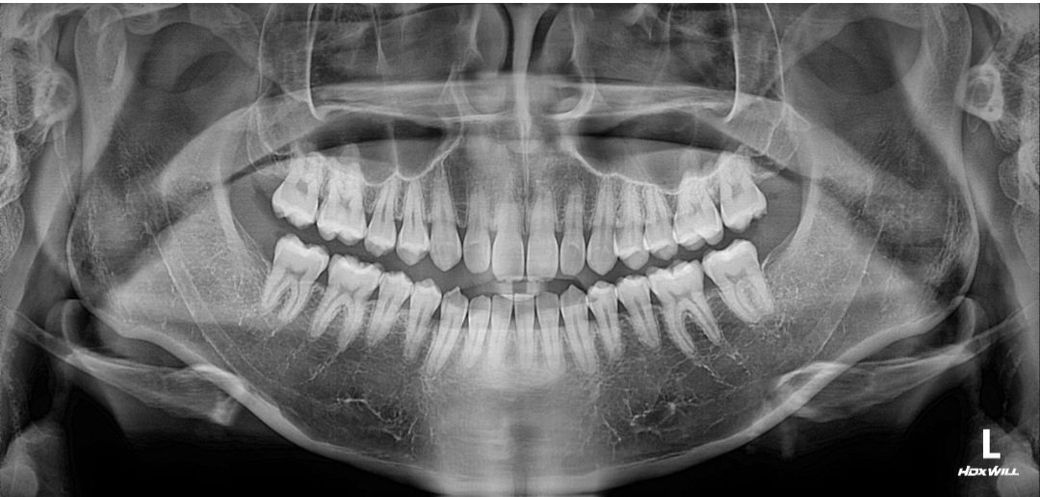

옆모습이 하악턱과 입이 튀어나와보여 컴플렉스 인 남성입니다 다른사람이 보기에는 어떨지는 모르겠습니다

그런데 미용적으로 개선하고싶으나 양악하기에는 부작용도 무섭고 수술도 무서워요 죽을수도 있다고 들어서요...그래서 고민하는게

1번 양악-가장드라마틱하게 턱도줄이고 입툭튀도 줄일수있을것같긴해요

2번 -발치교정하기에 치열이 아까운것같아 사랑니쪽으로 전체이동 비발치교정 하기-이러면 입툭튀 조금은들어간다고 들었어요 대신 입이들어가서 턱이 조금나와볼일수있다는데 치아 들어가도 2~3mm라 별차이 없을수도 있다고들어서...맞는지는 모르겠습니다

(현재 사랑니4개 없는상태입니다)

전문의가 평가하기에 1,2,3번중 어느게 맞을까요?

지난번에도 설명드렷지만 개인적으로는 아무것도 안하셔도될것같습니다. 크게 문제가 있어보이진 않아요. 하지만 작성자님께서 계속 글을 적으시는건 컴플렉스가 있어서 그런거 같으니 만약 치료를 원하신다면 양악케이스는 아닌것 같고 교정을 통해서 심미적인 부분을 해결하시는게 좋을것같습니다

개인적으로는 2번이 적당한것 같습니다.

1번은 위험부담이 크고, 3번은 미련이 남을것 같기 때문 입니다.